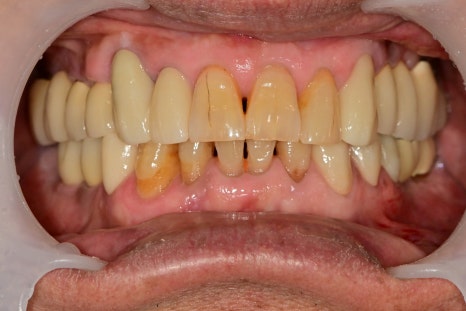

이제부터는 관리가 더 중요한 순간입니다.

관리라는 것은 특별한 것은 없습니다.

많이 들어보신 이야기들일 텐데요

식후 꼼꼼한 양치질

구강용품 사용을 통한 플라그 관리

딱딱하고 질긴 음식 주의

정기적인 내원으로 교합 평가

모든 경우가 이와 같을 순 없습니다만

임플란트를 하기에 앞서

자연치아를 좀 더 사용할 수 있는 상황이라면

시도해 보는 것도 좋은 방법이라고 생각합니다.^^